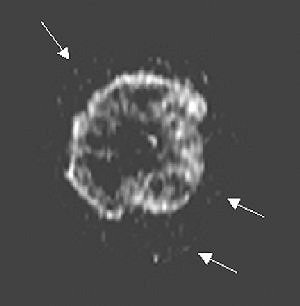

| Same patient. Above, parametric washout image shows tumor is isolated from rest of breast. Surrounding pixels (arrows) correspond to washout value smaller than 23 (i.e., cutoff value chosen by observer) and were there excluded from volume processing. Below, applying cutoff and processing volume of remaining pixels resulted in this parametric washout image. El Khoury C, Servois V, Thibault F, Tardivon A, Ollivier L, Meunier M, Allonier C, Neuenschwander S, "MR Quantification of the Washout Changes in Breast Tumors Under Preoperative Chemotherapy: Feasibility and Preliminary Results" (AJR 2005; 184:1499-1504).  |